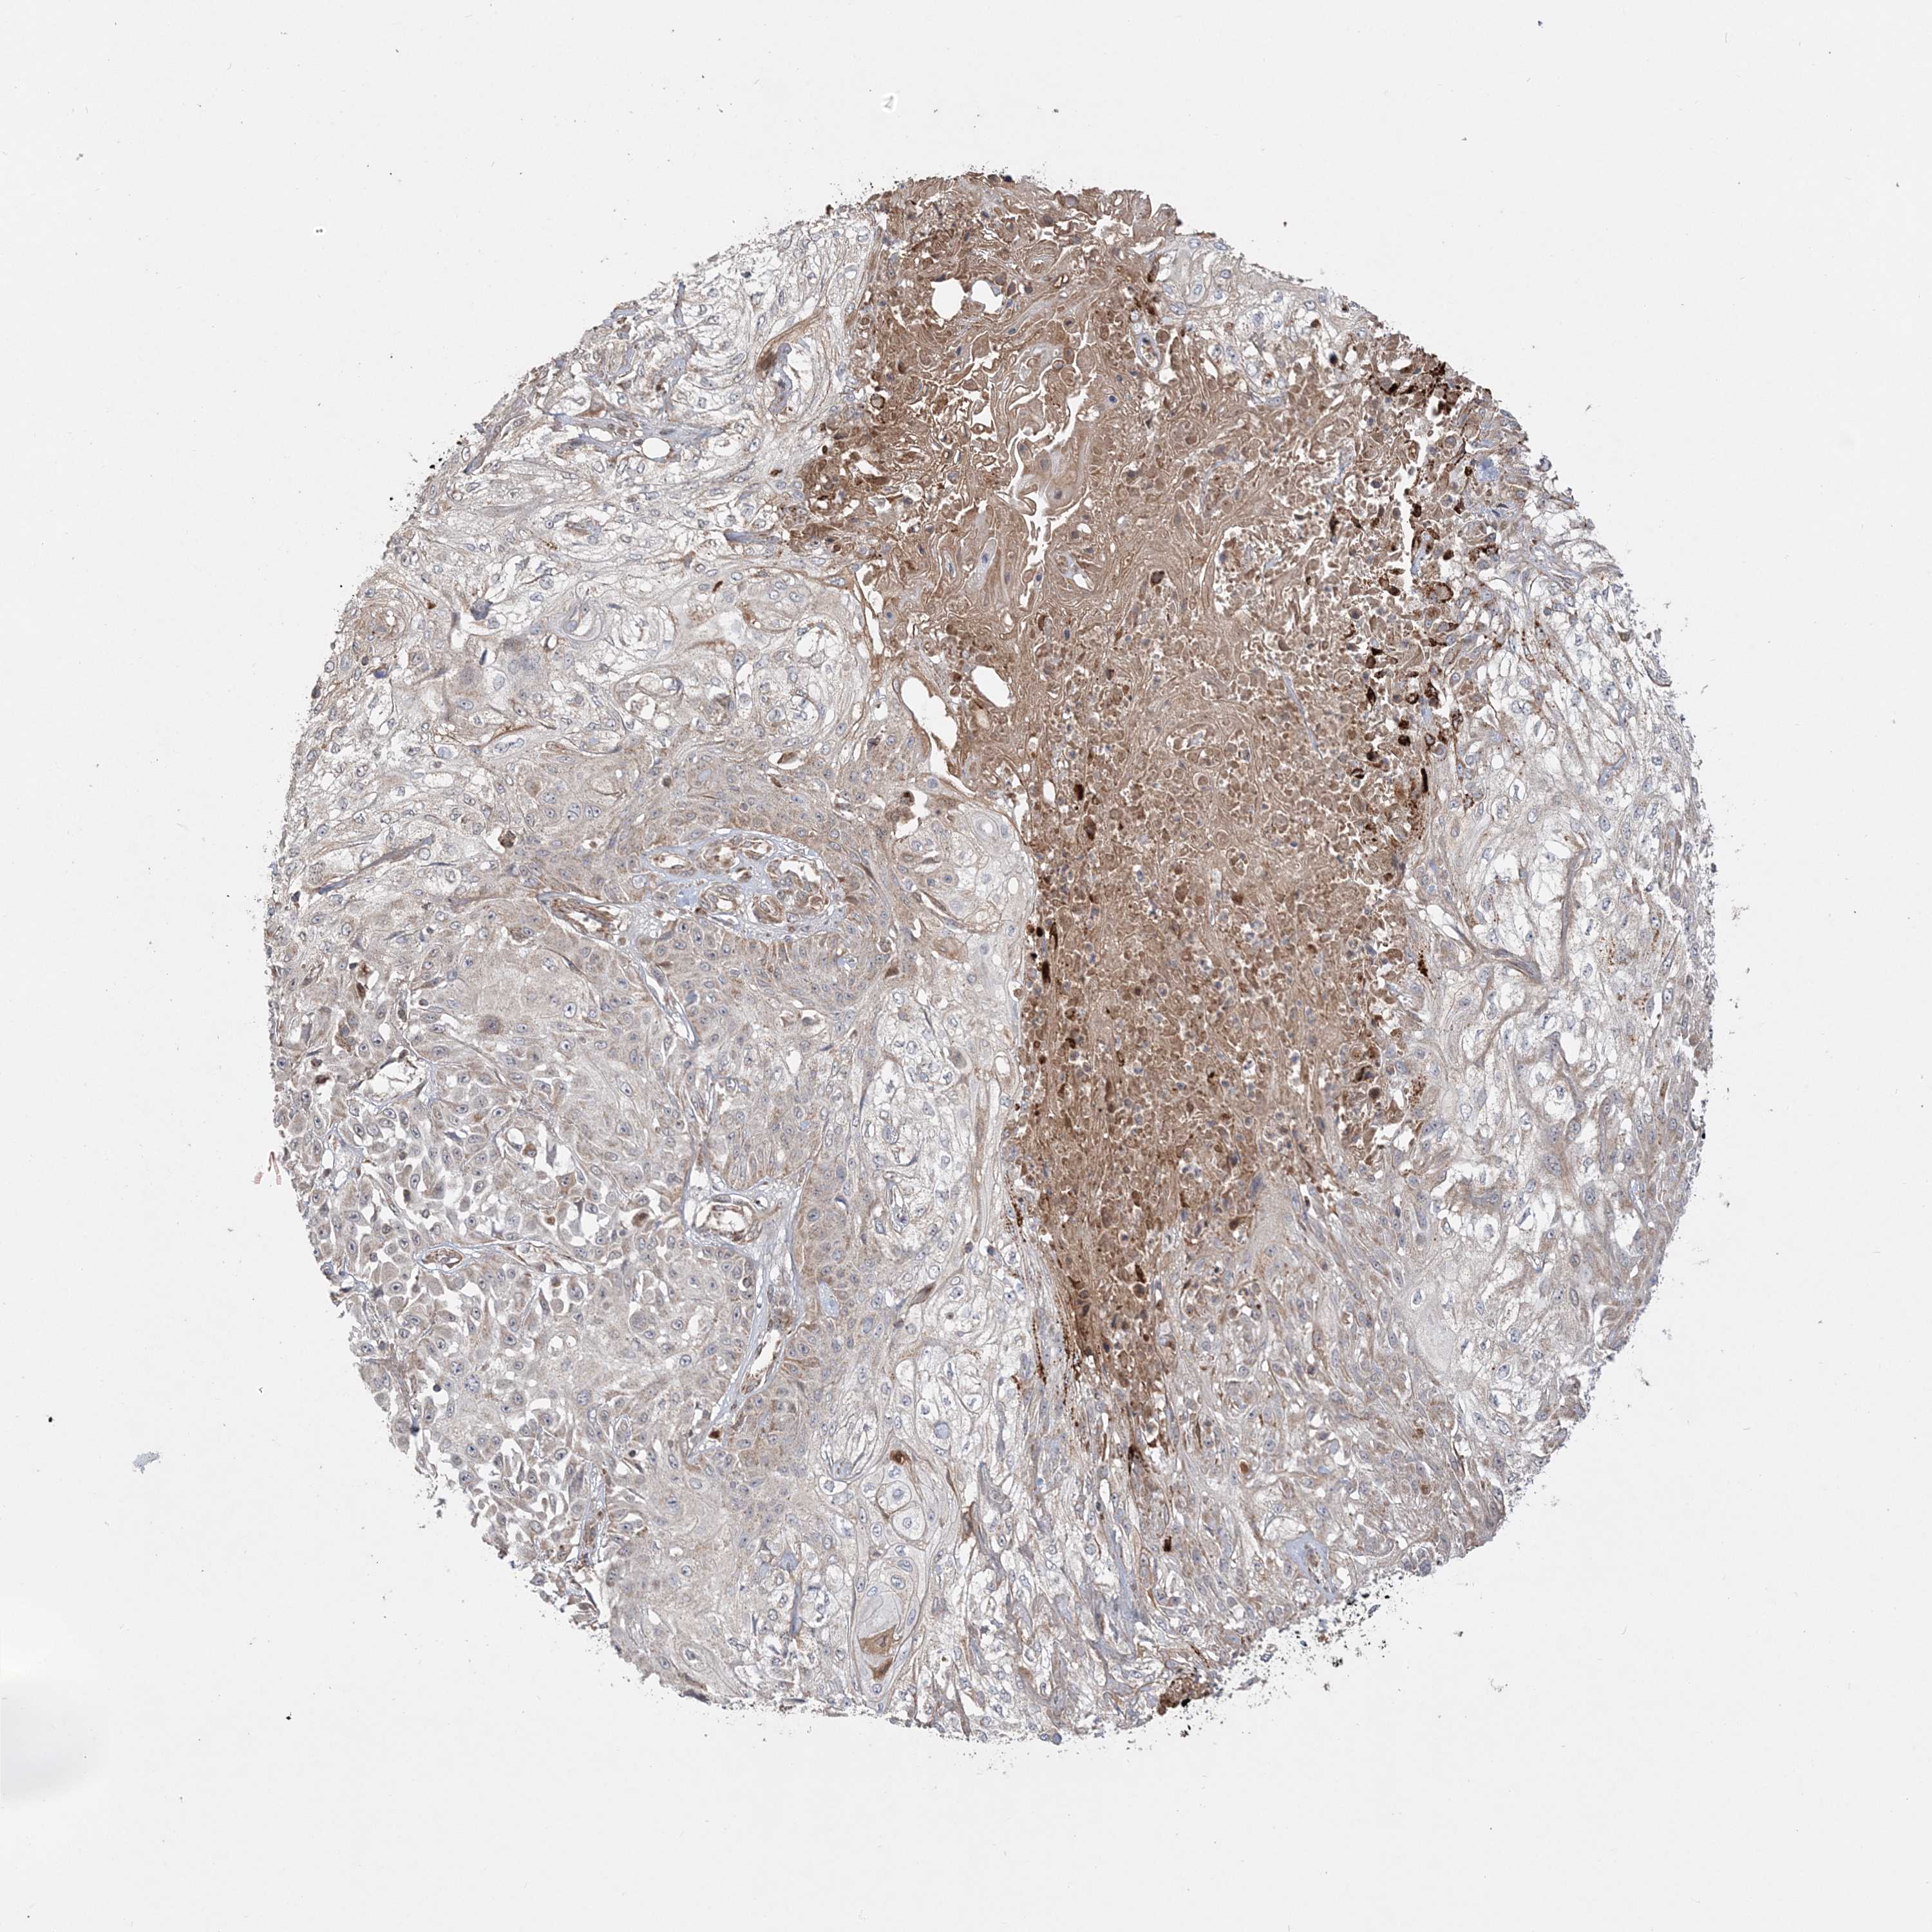

Basal cell and squamous cell cancer

SKIN CANCER - Protein expressioni

A mouse-over function shows sample information and annotation data. Click on an image to view it in a full screen mode. Samples can be filtered based on level of antibody staining by selecting one or several of the following categories: high, medium, low and not detected. The assay and annotation is described here.

Each image is clickable and will lead to virtual microscopy that enables deeper exploration of all samples and also displays staining intensity scores, fraction scores and subcellular localization as well as patient and tissue information for each sample.

Antibody HPA036560

Antibody HPA036561

Squamous cell carcinoma, metastatic, NOS